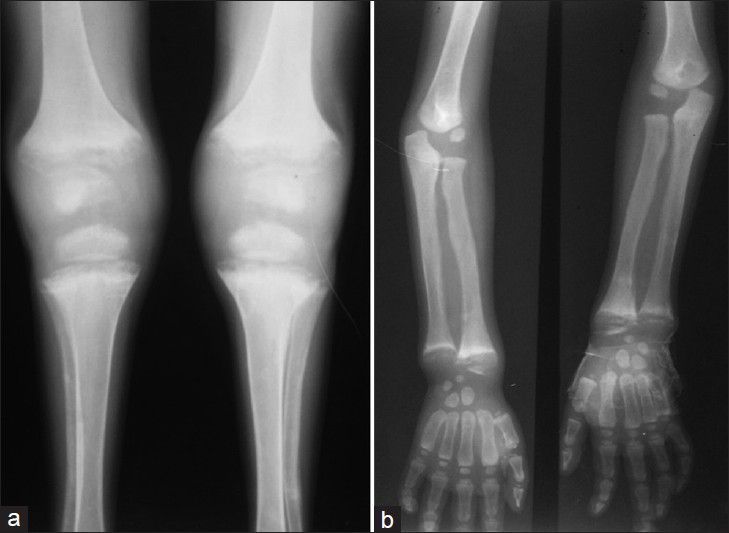

Figure 3.

X-ray (a) both knee and (b) wrist joint showing rickets-like changes

A 5-year-old marasmic male child was referred to our institute for multiple lymphadenopathy. His mother in the same household had pulmonary tuberculosis. On admission, the child had no history of cough, dyspnea or night sweats. However, he was lethargic and unable to stand or sit without support. His general examination was quite remarkable for the evidence of severe protein energy malnutrition (PEM) and rickets. He had marked pallor, generalized xerosis, crusted lesions with boil on the lower back, and hyperpigmented friction dermatosis on buttocks. His crawling movement was further complicated by valgus deformity of legs due to nutritional rickets. Cervical [Figure 1] and groin examination showed multiple matted lymph nodes forming a large cervical and inguinal lymphadenopathy. His ocular examination revealed nebular keratopathy in both eyes. His initial evaluation at the previous institute did not reveal any malignancy as a possible etiology for large cervical and inguinal lymphadenopathy. His detailed clinical neurological evaluation did not reveal any positive findings. Hematological investigation revealed severe anemia (Hemoglobin - 7.3 gm/dl), leukocytosis (Total Leukocytes Count - 15,700/mm3; 84% neutrophils, 12% lymphocytes, 3% monocytes, and 1% eosinophils), and mild thrombocytopenia (87,000/mm3). Biochemical investigation for rickets showed hypocalcemia (serum calcium - 6.31 mg/dl), normal phosphate (serum phosphate - 4 mg/dl), higher alkaline phosphate - 310, and low Serum 25 (OH) D - 8 ng/ml. He was seronegative for human immunodeficiency virus (HIV) on Enzyme-Linked Immunosorbent Assay (ELISA) test; Mantoux test was also negative. The chest X-ray revealed miliary Koch's infiltration with a widening of the costochondral junction of the ribs due to rickets in the bony thorax [Figure 2]. Abdominal and thoracic ultrasound revealed mild hepatomegaly, mild splenomegaly, and enlarged mesenteric, inguinal, peripancreatic, celiac axis, periportal, and bilateral iliac lymph nodes. Corroborative radiological evaluation for rickets (X-ray both knee and wrist joint) showed metaphyseal widening with splaying and fraying of epiphysis and changes related to osteoporosis, and pencil line thinning of the epiphyseal cortex, suggesting rickets [Figure 3]. Fine needle aspiration cytology of cervical lymph node showed features of tuberculous lymphadenitis with the presence of acid-fast bacilli.